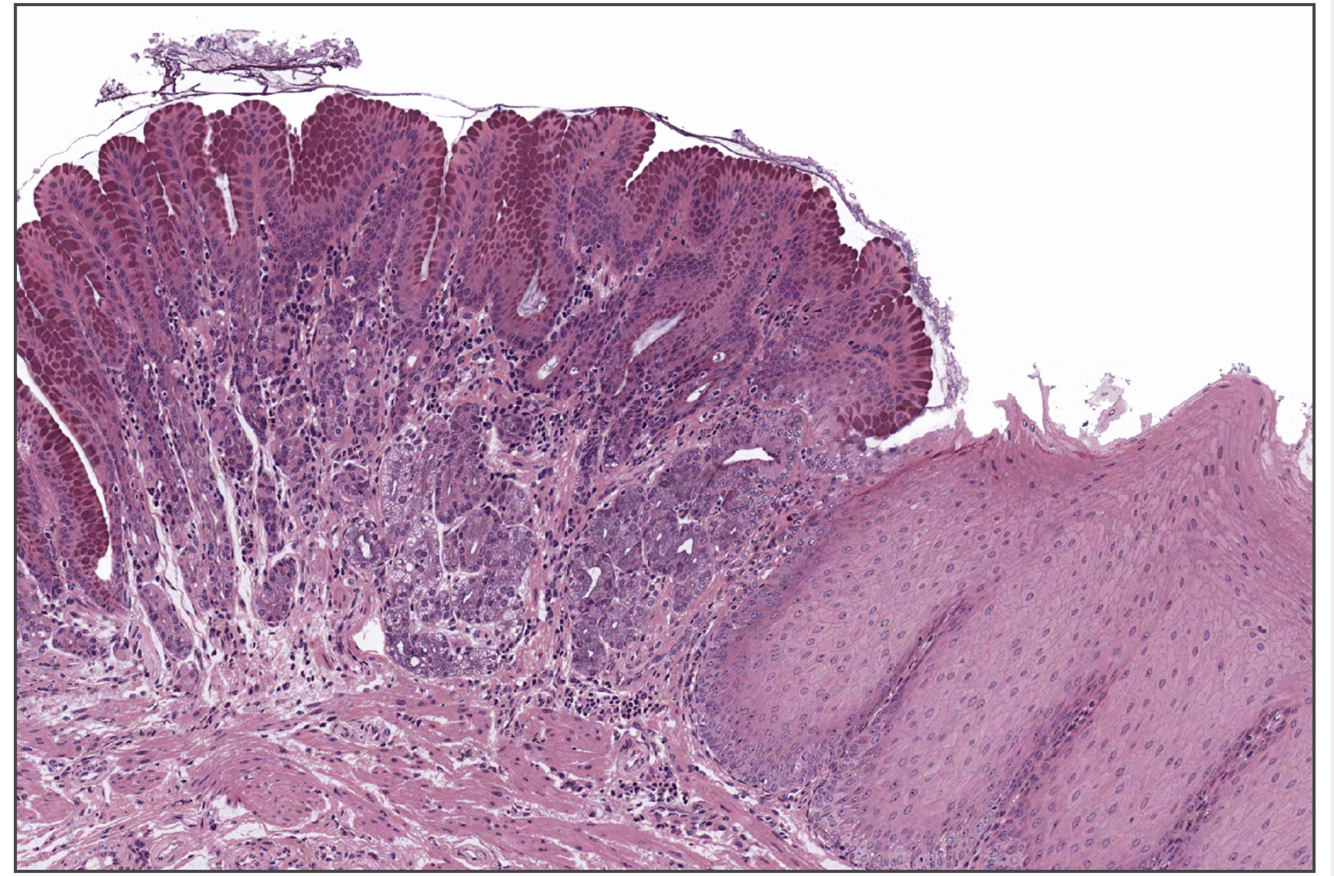

21

Q

What is this

A

It is the oesophagastric junction - stratified squamous moist (esophagus) to simple columnar (cardiac stomach),